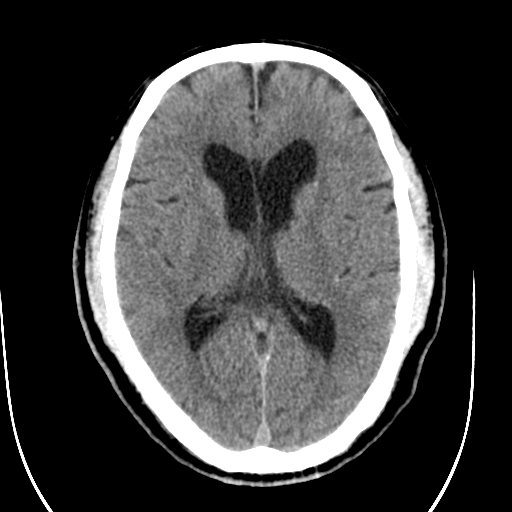

标题: CT28335:男,58岁,请各位看看是不是有脑积水,蝶窦内高密 [打印本页]

标题: CT28335:男,58岁,请各位看看是不是有脑积水,蝶窦内高密

轻度积水,蝶窦正常。

脑积水!建议行mri!

1)脑积水。2)副鼻窦炎。